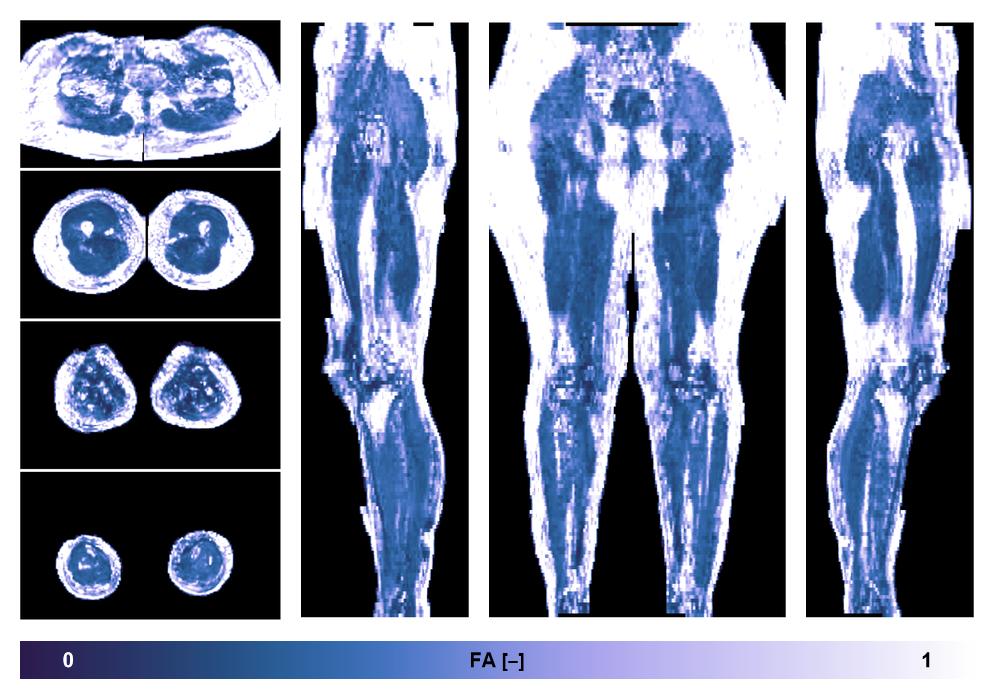

• Fractional anisotropy

IVIM corrected whole leg muscle fractional anisotropy obtained from diffusion tensor imaging.